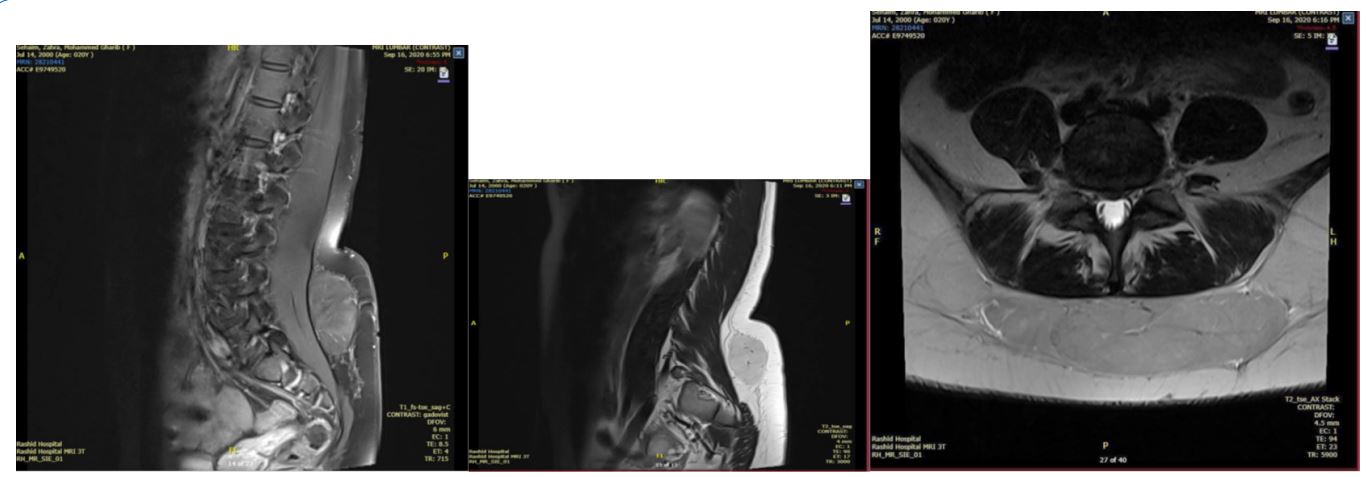

A 19-year-old Emirati female, a known case of disc prolapse, presented complaining of lower back swelling for one year. On examination, the patient looked alert, and oriented with a BMI of 20.4, and was hemodynamically stable. Local examination revealed a soft, non-tender 4x5 cm lower back lump above the natal cleft. Routine blood investigations were within normal range; targeted ultrasound suggested benign morphology soft tissue fibromuscular lipoma. MRI revealed an atypical lipoma in the subcutaneous region of the back at the level of L4-15 vertebra with disc herniation at the same level.

Figure 2: MRI at L5/S1: A large, well-defined T2 hyper-intense lesion measuring about 12 cm in transverse, 3 cm in anteroposterior, and 9 cm at the craniocaudal dimension with thin septa and blood vessels traversing through it, in the subcutaneous region of the back at the level of L4-L5 vertebra with disc herniation at the same level. Under GA, complete surgical excision was done. The postoperative course was uneventful. The patient was discharged the next day. Histopathology biopsy revealed: a yellow-colored nodular lobulated mass weighing 145.0 gm and measuring 11.5 x 9.4 x 3.2 cm. Slicing revealed lobules of adipose tissue.